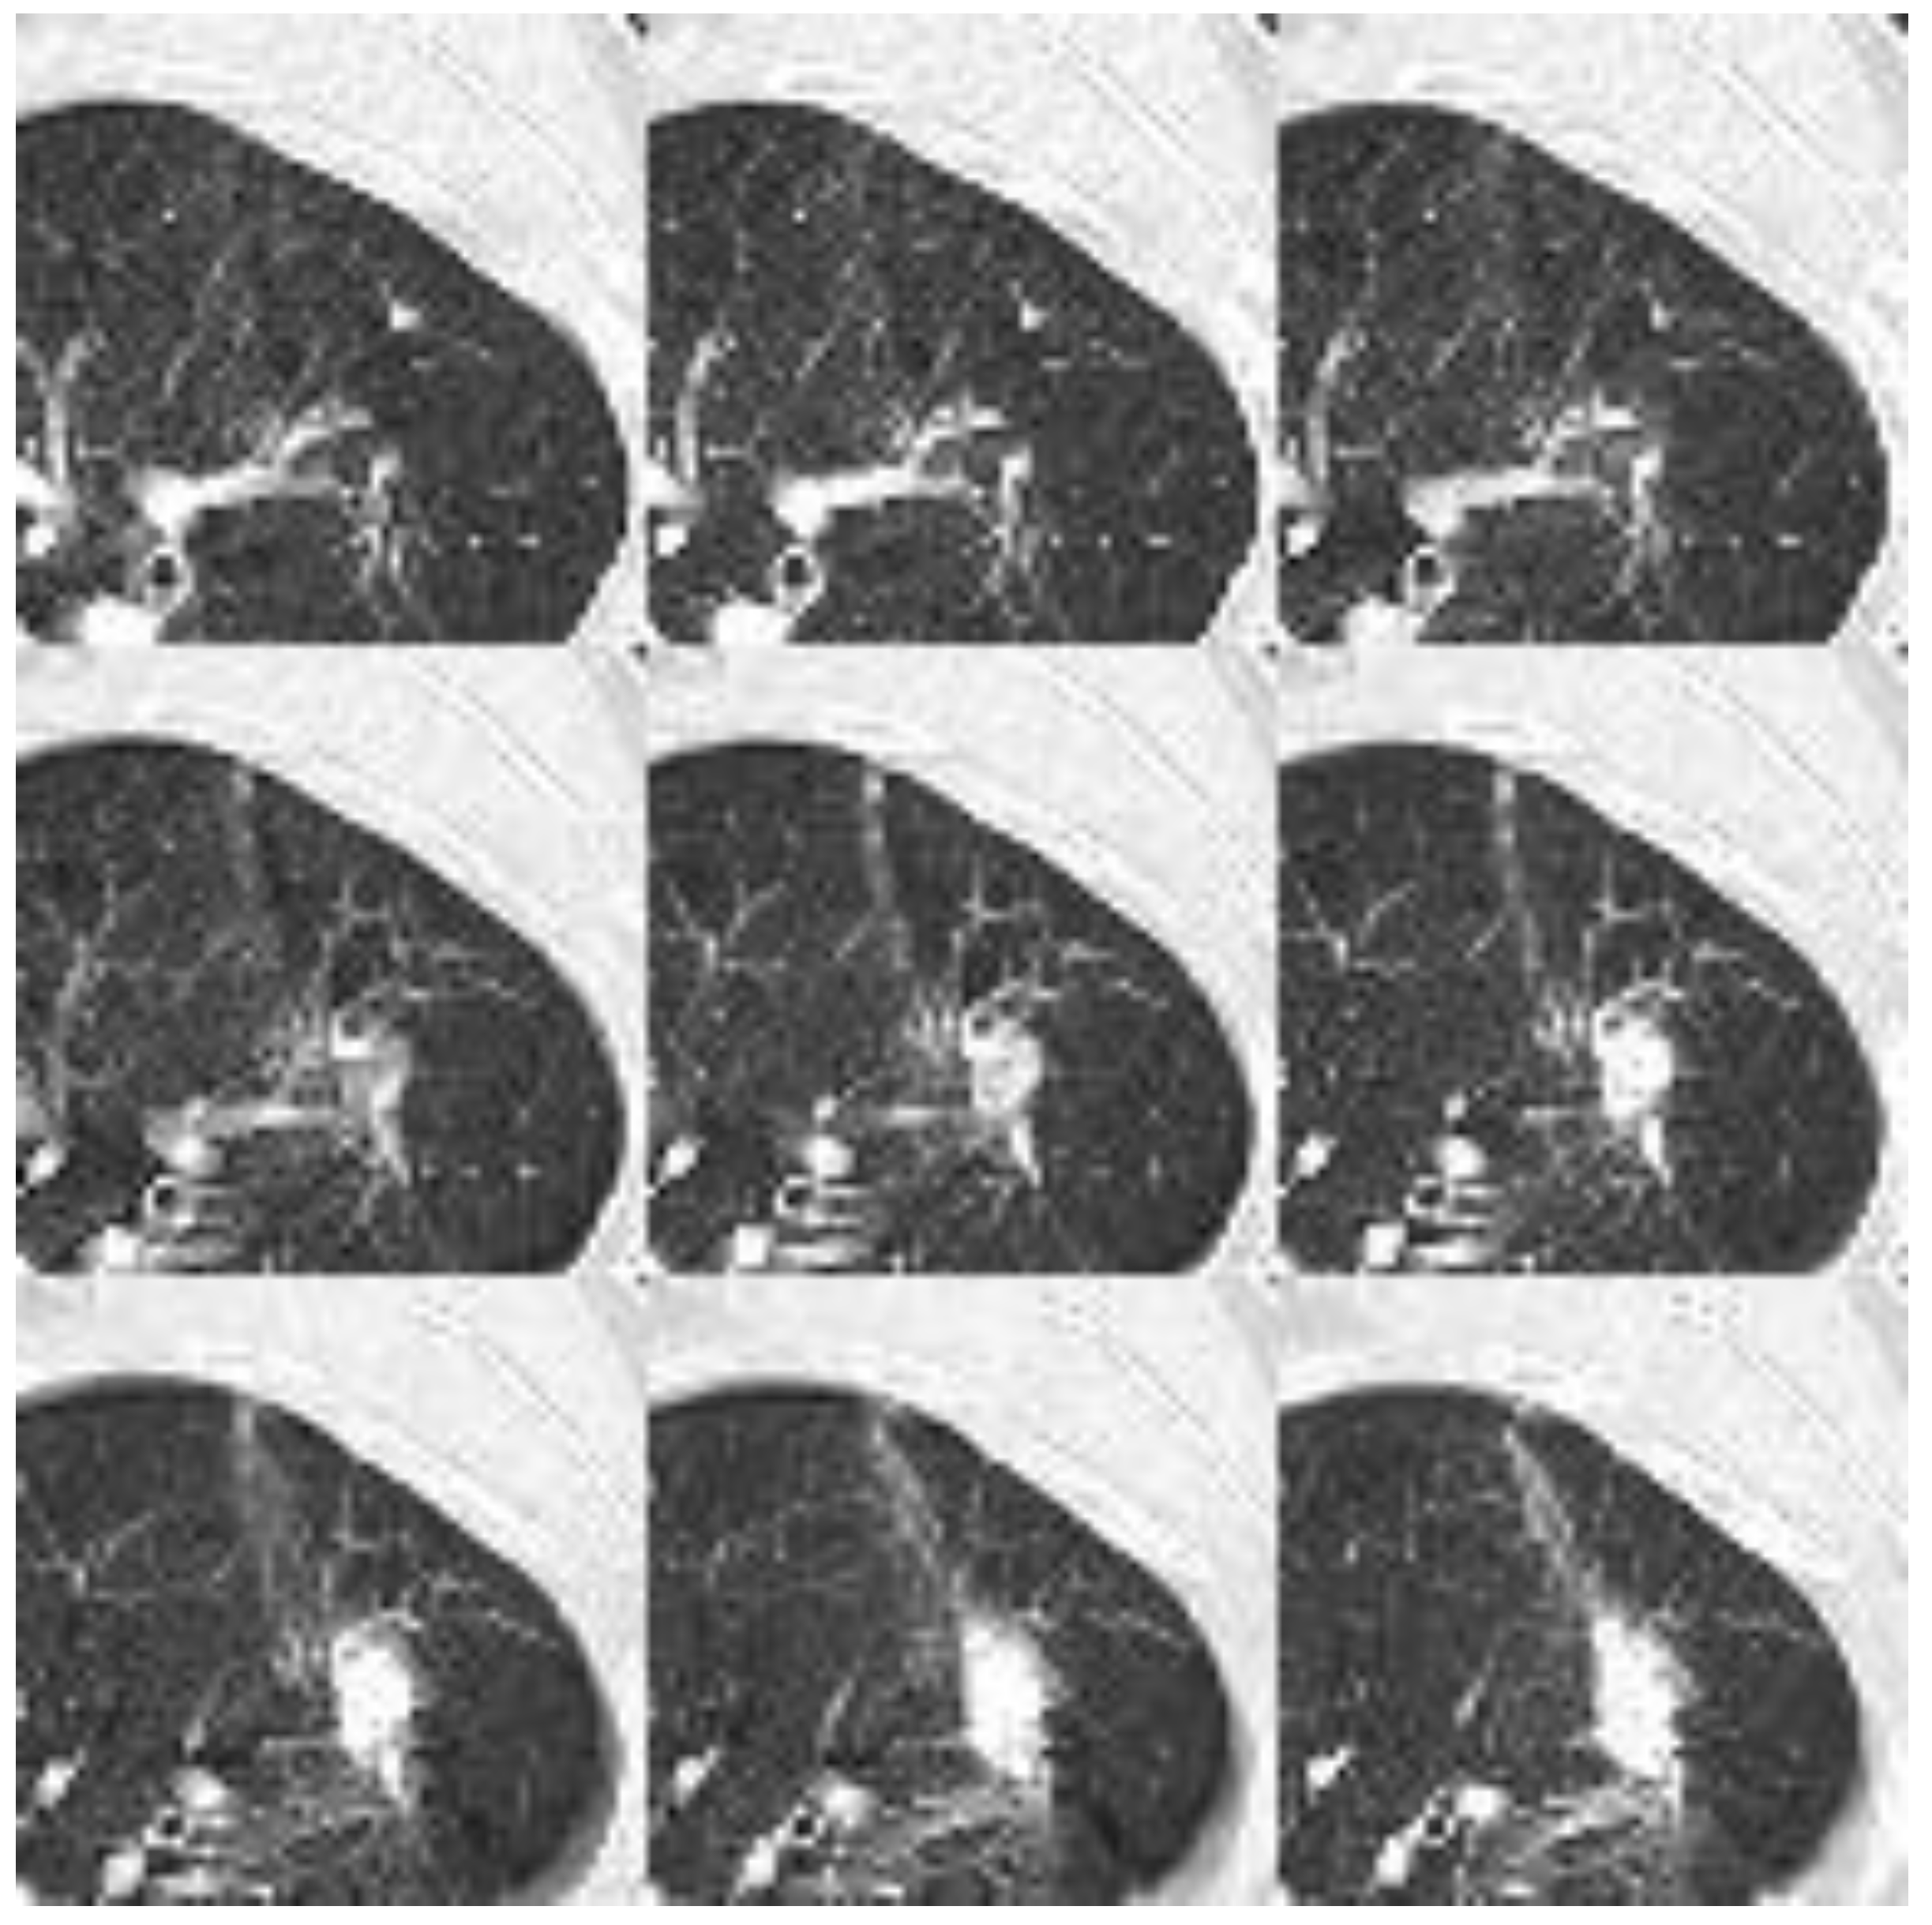

Figure 7. demonstrates the input for 2D NN. As described in the methods section, each CT image has been transformed into uint8 (unsigned integer 8-bit) format using a lung window. The nodule is positioned at the center of a patch with a dimension of 64×64. Nine such patches are flattened to form an input image with a dimension of 192×192 for the 2D neural network, while for the 3D neural network, they are stacked into a dimension of 9×64×64.

Figure 7. : Nine patches are flattened to a dimension of 192×192 for the 2D neural network input. The data format is uint8.